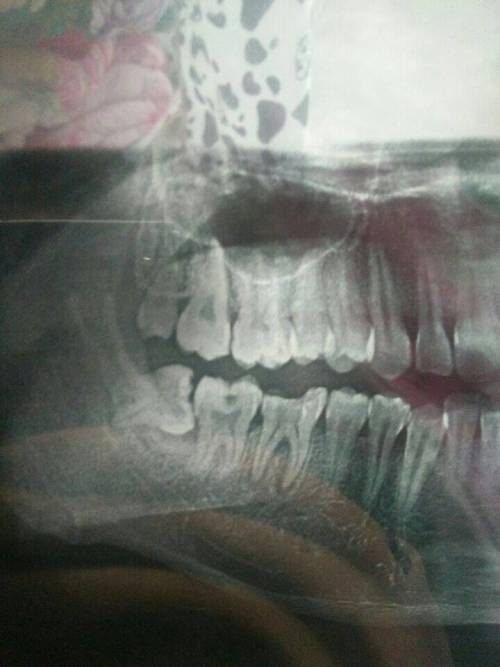

1、術前檢查:拔智齒前需要進行口腔檢查、X光片等檢查,以了解智齒的位置和周圍結構,這些檢查費用也是拔智齒總費用的一部分。